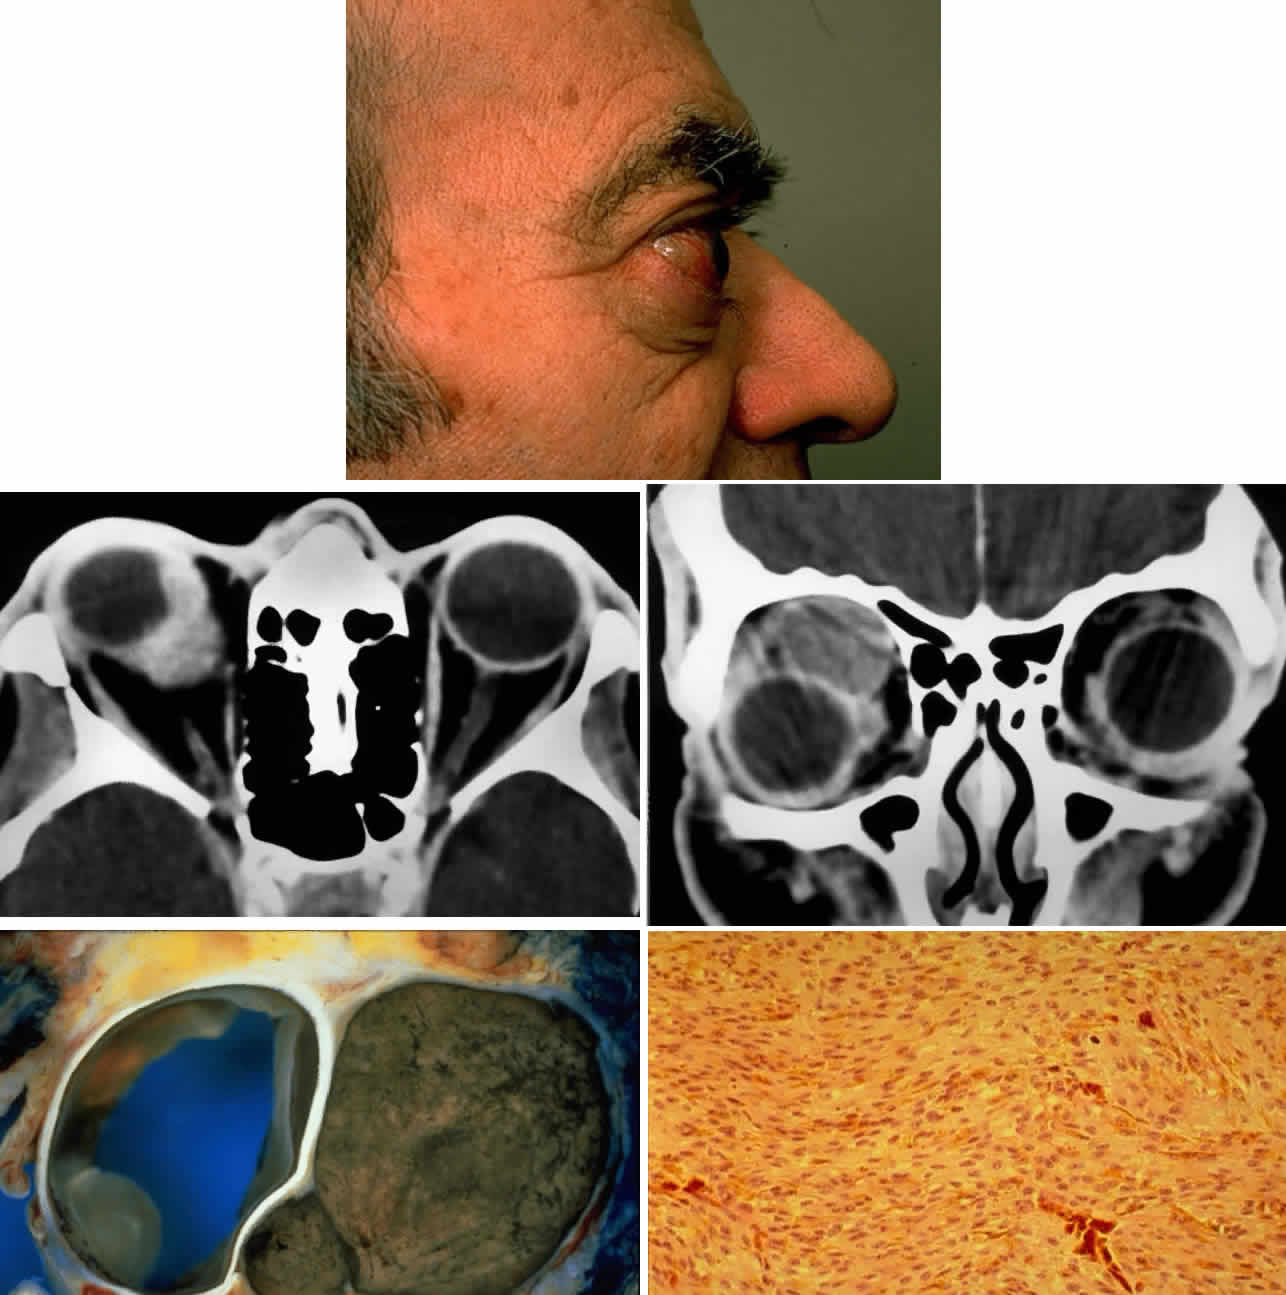

Radiologic findings consist of either focal or widespread destruction of the sinuses, with invasion of the adjacent structures by a solid tumor mass (Fig. 2). The mass is usually large; however, sometimes it may be relatively small but may extend to adjacent structures, particularly in the case of adenoid cystic carcinoma (Fig. 3). The sinus and orbit may be the only structures involved, but there is frequently extension to the base of the skull.

Fig. 2. A 32-year-old woman presented with a 1-month history of sinus congestion and nasal obstruction unresponsive to antibiotics. In the 1 week preceding the initial exam, the right eye became progressively more prominent and showed tearing and redness. On examination, there was mild edema of the lower lid and dysesthesia in the distribution of cranial nerve V2, and the globe was displaced 6 mm laterally and 5 mm anteriorly. There was mild limitation of abduction, chemosis, and nasal choroidal folds. An axial CT scan revealed a diffuse, destructive soft tissue mass centered in the superior nasal passage and ethmoid sinuses extending into the right orbit in contiguity with the medial rectus (A). On enhanced coronal view, the tumor was noted to involve the right maxillary antrum and to extend superiorly into the anterior cranial fossa (B). Biopsy of the sinus (C) revealed an alveolar-type rhabdomyosarcoma (muscle stain, × 320).

Fig. 3. A 73-year-old man presented with a 2-year history of infraorbital numbness and burning sensation, which had progressed to include the supraorbital region, forehead, and lower face during the past 6 months. He had been treated with radiotherapy for prostate carcinoma 7 months before orbital presentation. Examination was significant for proptosis of 2 mm and dysesthesia, including corneal numbness, in all three divisions of cranial nerve V. CT scan revealed a soft tissue mass in the inferior orbit contiguous with the inferior rectus muscle (A). The lesion extended through the infraorbital canal to involve the pterygopalatine fossa and was associated with soft tissue hanging into the upper portion of the maxillary sinus. An axial CT scan-guided aspiration biopsy was performed (B) and revealed squamous cell carcinoma. Groups of cohesive malignant squamous epithelial cells (C) were noted to have pleomorphic nuclei and abundant eosinophilic to orange cytoplasm, with no features of mucinous differentiation (H & E, × 320). (C from White VA, Rootman J: Orbital pathology. In Albert DM, Jakobiec FA (eds): Principles and Practice of Ophthalmology, Vol 4, p 2342. Philadelphia, WB Saunders, 1994.)